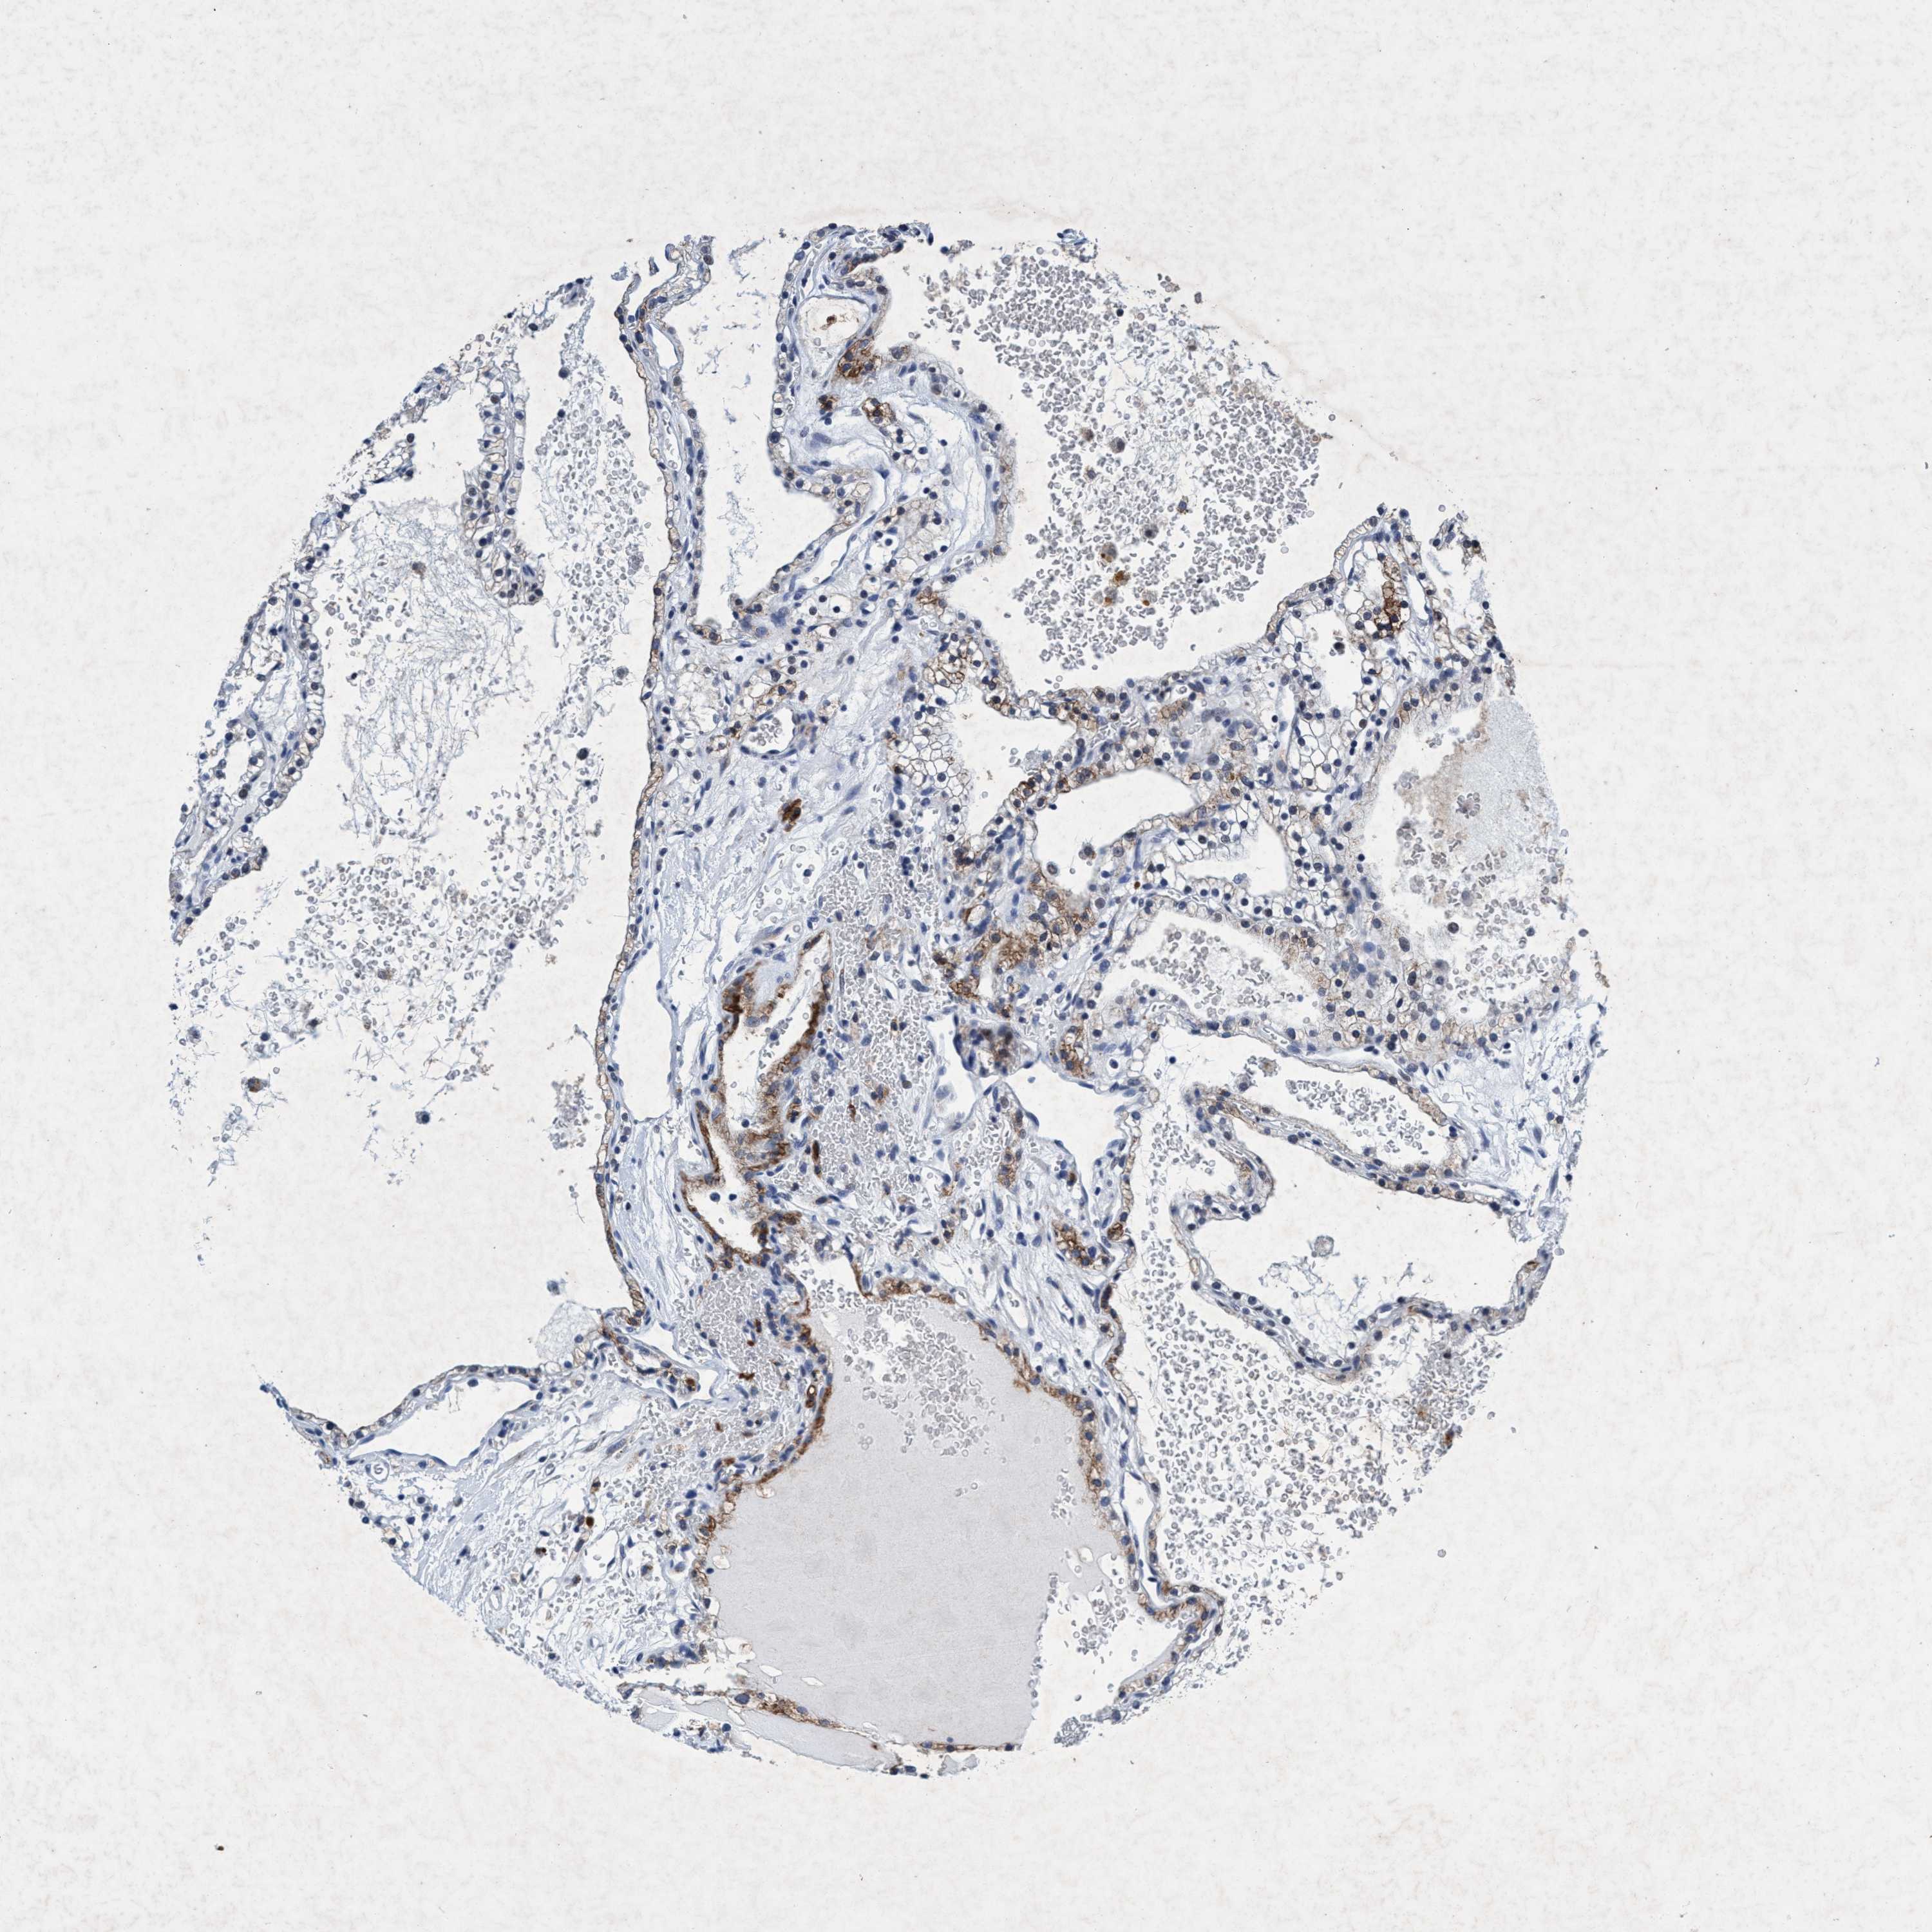

KIDNEY RENAL PAPILLARY CELL CARCINOMA (TCGA) - Interactive survival scatter ploti

& Survival analysisi

GRB14 is not prognostic in Kidney Renal Papillary Cell Carcinoma (TCGA)

: 0.94